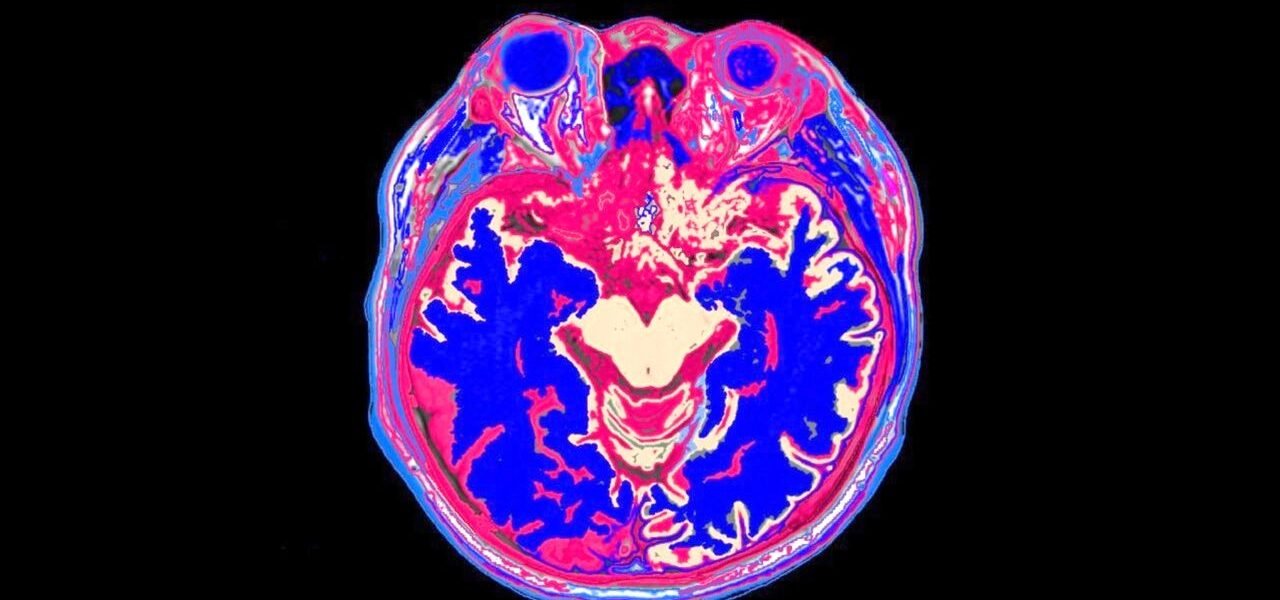

Con ese banco de imágenes y los informes de deterioro cognitivo, los científicos entrenaron un modelo de aprendizaje automático llamado DunedinPACNI para aprender “cómo luce” el envejecimiento en una tomografía, tomando en cuenta características clave como el grosor de la corteza cerebral o el volumen de la materia gris.

Nuevos sistemas basados en inteligencia artificial, como el modelo DunedinPACNI, buscan medir la edad biológica del cerebro mediante resonancias magnéticas. Aunque aún no están aprobados para uso clínico, estos escáneres podrían permitir evaluar el estado del órgano y anticipar riesgos de enfermedades neurodegenerativas como la demencia, incluso antes de que se manifiesten síntomas claros.